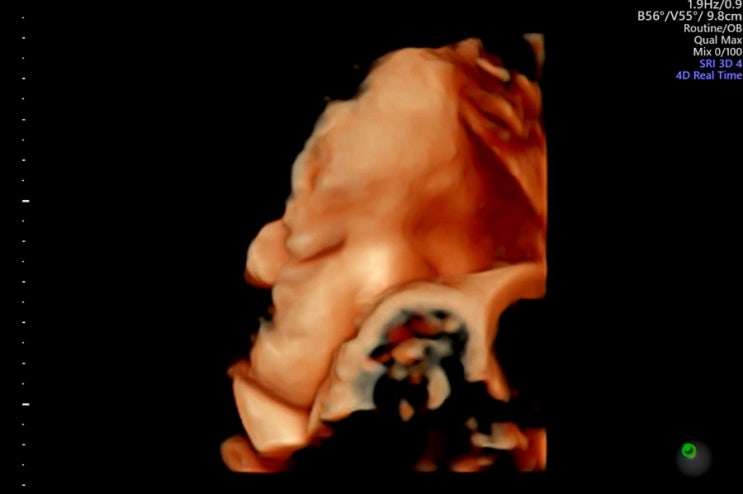

[임신일기 13] 임신 34주 증상 / 35주 여수시 보건소 지원 서비스 신청 / 36주 막달 검사

34주차 이제 슬슬 운전하고 다니는 게 힘들어지는 중! 오래 앉아있으면 방토가 자리 좁다고 자꾸 갈비뼈를 ...